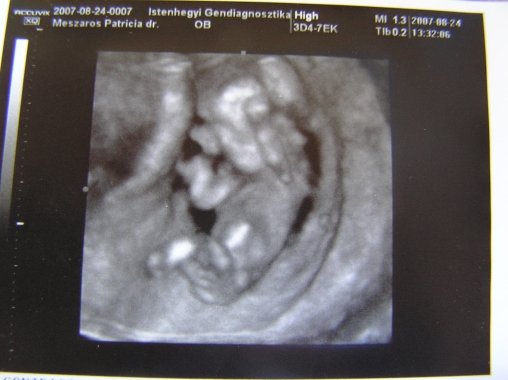

A második képen nyitva van a szeme is